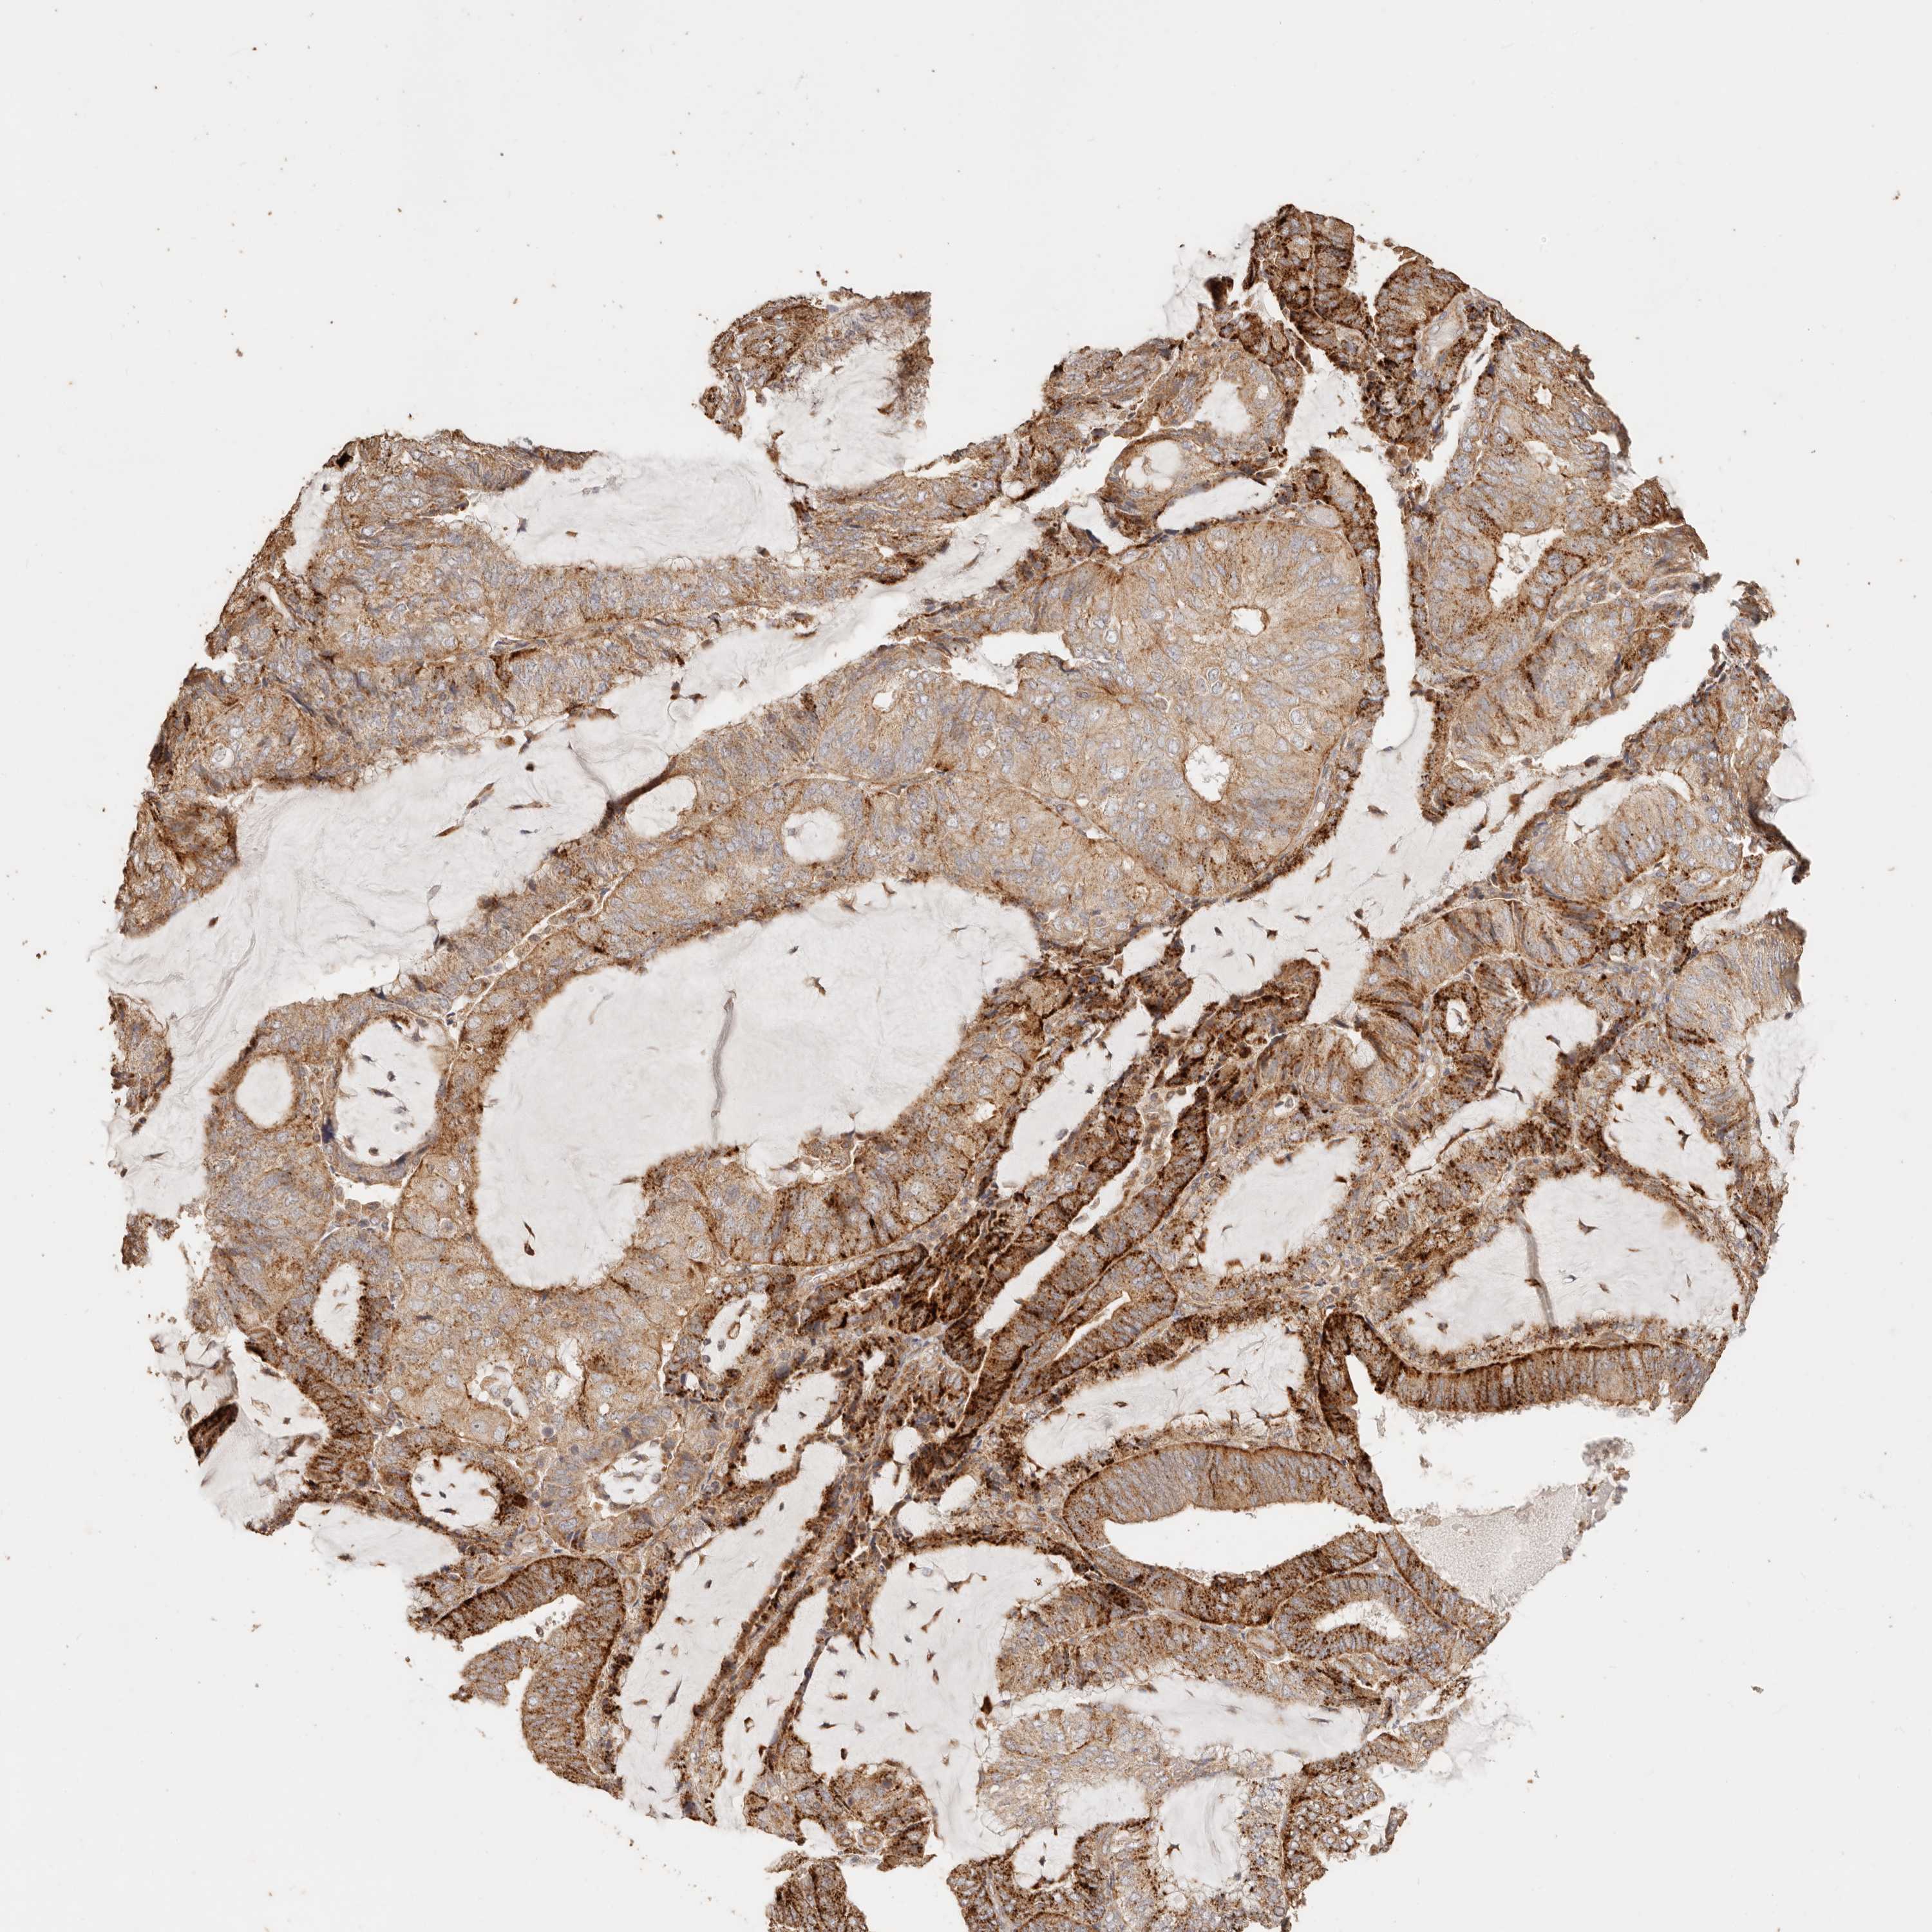

ENDOMETRIAL CANCER - Protein expressioni

A mouse-over function shows sample information and annotation data. Click on an image to view it in a full screen mode. Samples can be filtered based on level of antibody staining by selecting one or several of the following categories: high, medium, low and not detected. The assay and annotation is described here.

Note that samples used for immunohistochemistry by the Human Protein Atlas do not correspond to samples in the TCGA dataset.

Antibody stainingi

Antibody staining in the annotated cell types in the current human tissue is reported as not detected, low, medium, or high, based on conventional immunohistochemistry profiling in selected tissues. This score is based on the combination of the staining intensity and fraction of stained cells.

Each image is clickable and will lead to virtual microscopy that enables deeper exploration of all samples and also displays staining intensity scores, fraction scores and subcellular localization as well as patient and tissue information for each sample.

Antibody HPA004912

Antibody HPA013350

Antibody CAB012209

Staining

High

Medium

Low

Not detected

Intensity

Strong

Moderate

Weak

Negative

Quantity

>75%

75%-25%

<25%

None

Location

Nuclear

Cytoplasmic/membranous

Cytoplasmic/membranous,nuclear

Adenocarcinoma, NOS

Adenocarcinoma, metastatic, NOS